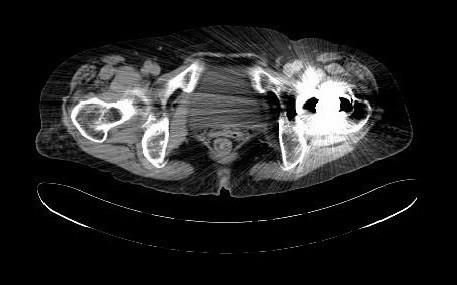

查体:专科:左髋部后外侧陈旧手术瘢痕,左髋关节前方压痛、无轴向叩击痛阴性,无大转子叩击痛,双下肢感觉及血运均正常。双下肢肌力V级。动量:右髋内外旋诱发疼痛,屈曲90度疼痛。外旋明显滚动试验阴性,左髋4字试验阳性。双下肢等长。左髋关节屈90°,伸0°,外展40°,内收20°,内旋30°外旋10°。右髋关节屈120°,伸直0°,外展40°,内收20°,内旋30°外旋30°。 辅助检查:2010-12-08 ESR 6.0mm/h,2011-01-04外院CRP8.5mg/l(参考范围0-10mg/l)X线示左双动股骨头置换术后,假体松动、下沉,髓腔内可见骨水泥影。近端干骺端骨质明显缺损。髓腔内侧皮质形态不规则。

诊断:左双动股骨头置换术后假体松动、下沉、股骨骨缺损(PaproskyII型) 治疗:患者在全麻下左双动股骨头假体取出+同种异体骨植骨+左全髋关节翻修术,术后予以抗炎(二联)+抗凝+镇痛+护胃+补液等治疗,并予以抗骨质疏松药物